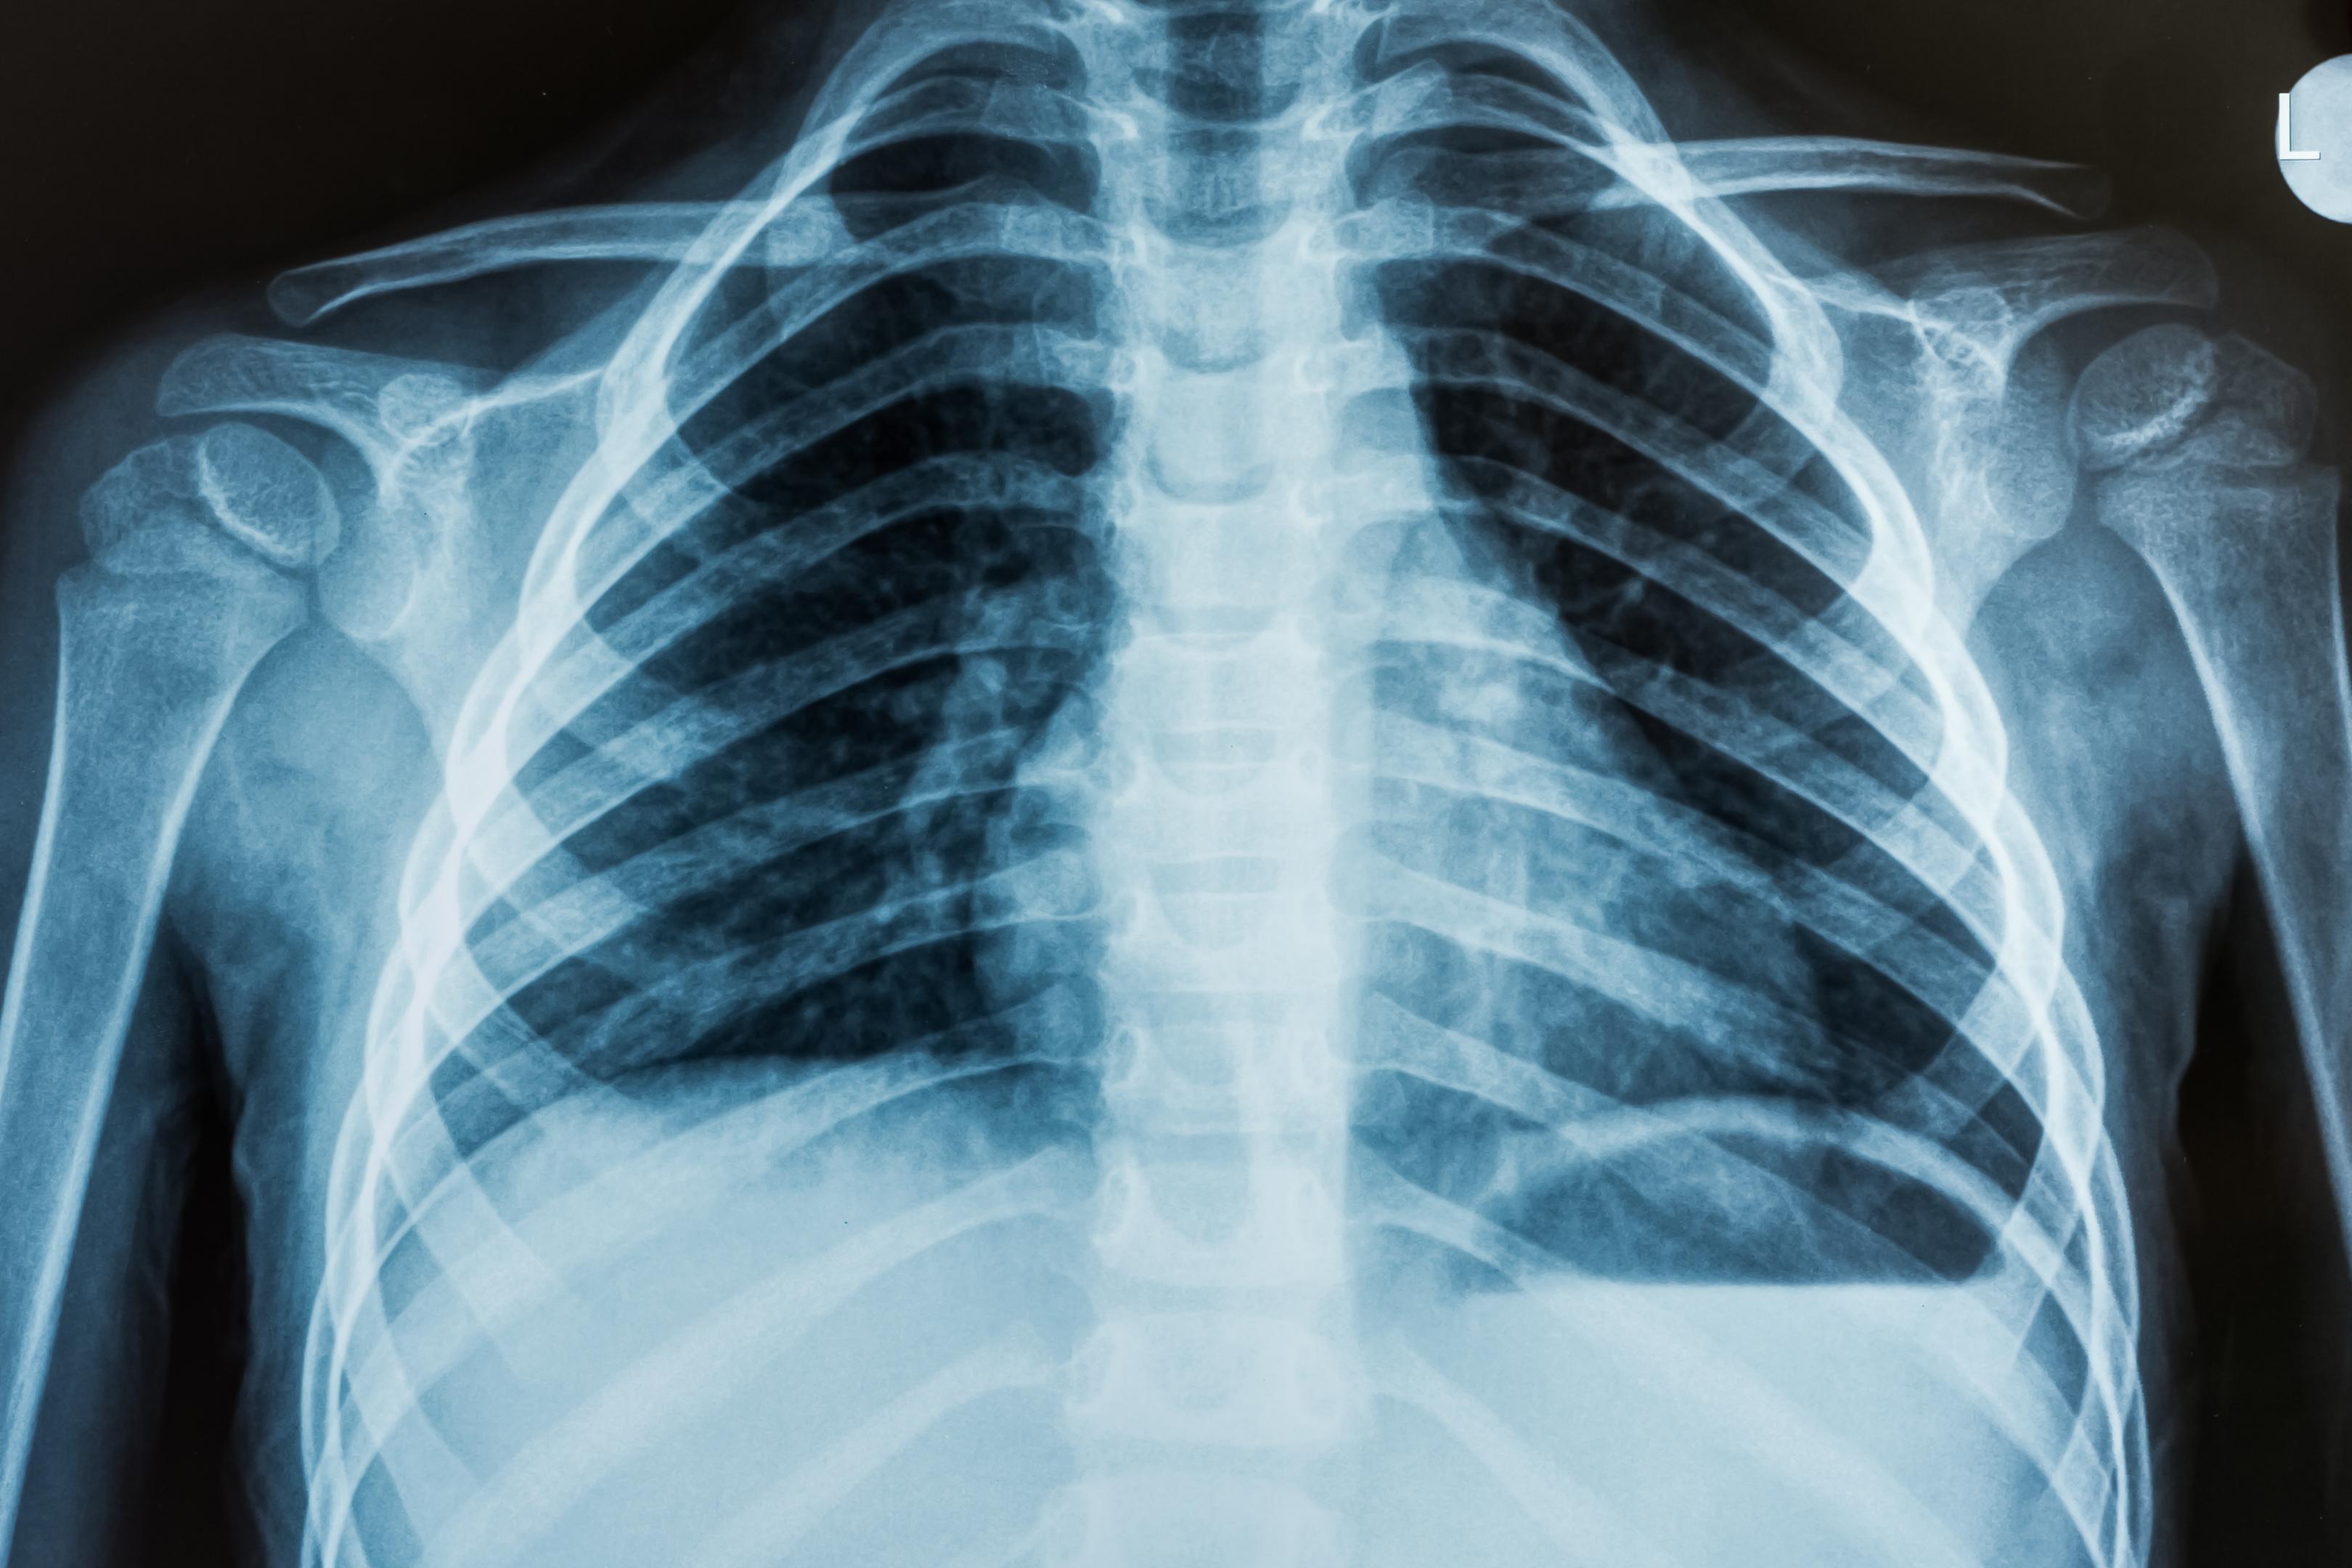

Снимок грудной клетки здорового ребенка: примеры и диагностика

Раздел: Мудрость в объективе